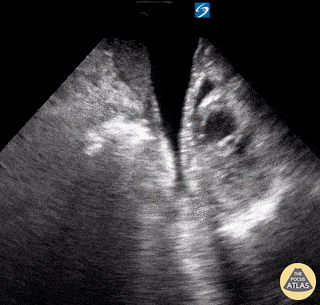

Shown here is an image acquired while performing a RUSH exam on a 40-year-old female who presented in shock. HPI notable for SOB and worsening abdominal distention x5 days; PMH of decompensated etoh cirrhosis. Vitals included BP 80/40; HR 110; RR 30; O2 sat 90% RA. Seen here is the image obtained while performing subcostal sweep from base to apex. It is most notable for a dilated, hypokinetic RV with paradoxical septal motion and an underfilled, hyperdynamic LV. There is also intraperitoneal free fluid appreciated. Subsequent CT chest confirmed presence of large, bilateral pulmonary emboli as etiology of patient’s shock. David Carroll